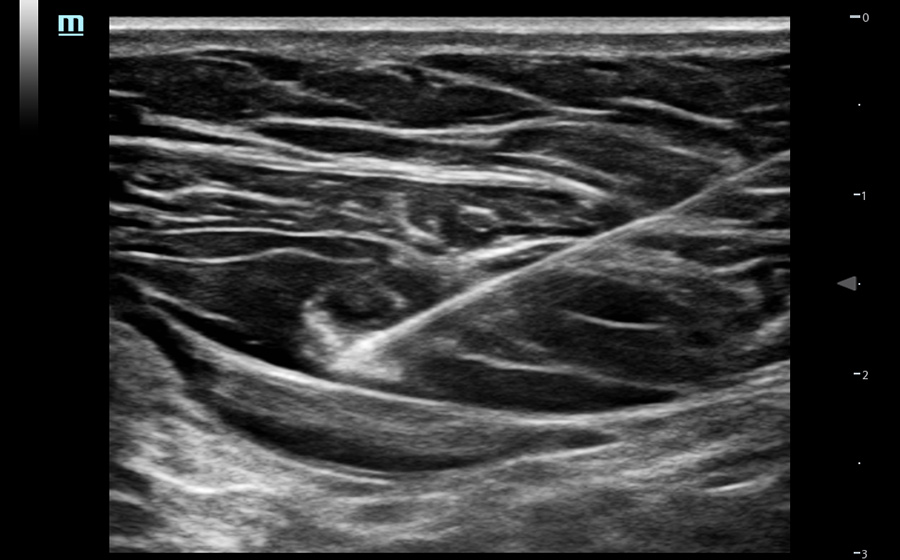

Funkcje wspomagaj?ce operatora podczas wk?u?

Obrazy kliniczne